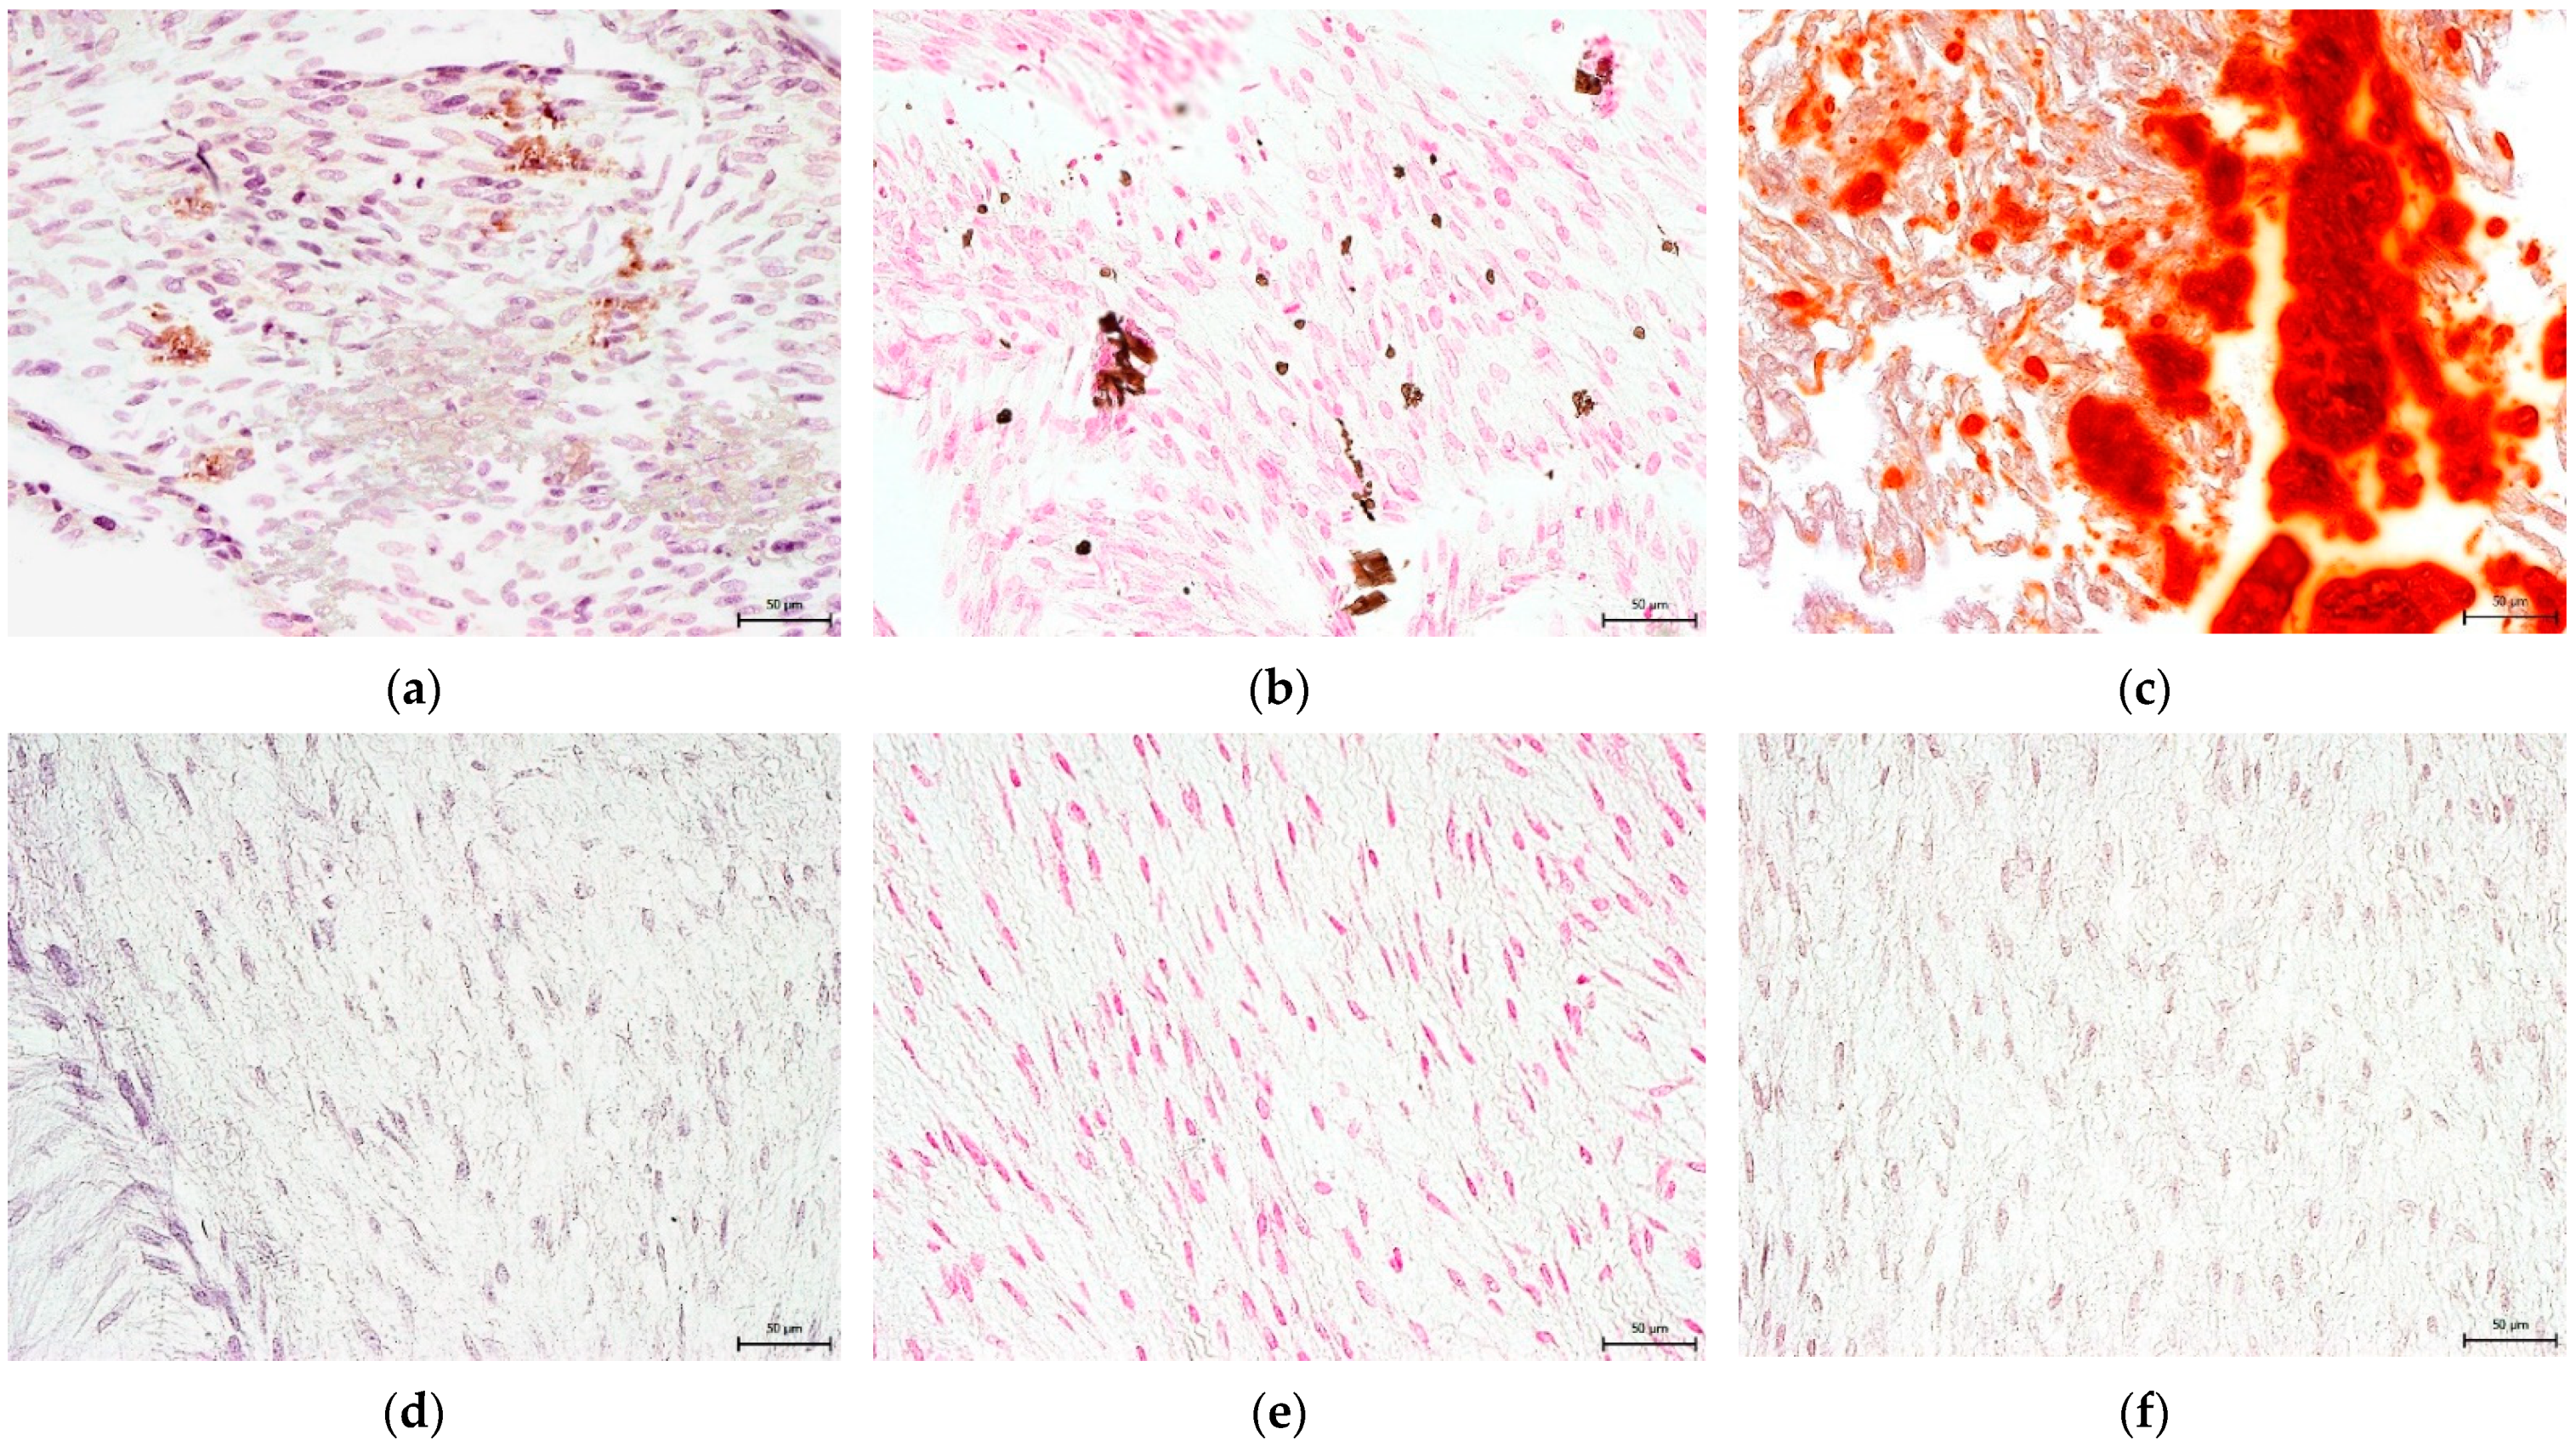

3.4. Effect on hNDP-SC Multipotency

2.6.1. Osteogenic Differentiation In Vitro

2.6.2. Chondrogenic Differentiation In Vitro

2.6.3. Adipogenic Differentiation In Vitro